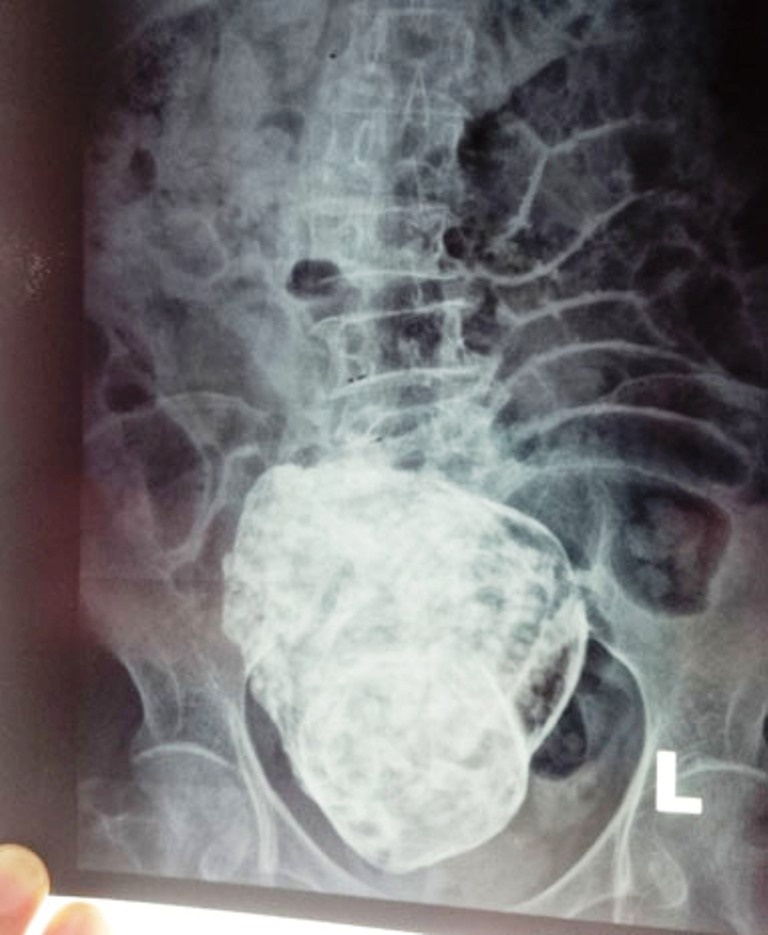

| Ảnh chụp X quang bệnh nhân N.T.S. |

Về phía bệnh viện Cam Ranh, Phó giám đốc Lê Quang Vinh cho biết khám lâm sàng thấy bụng mềm, có sẹo mổ lấy thai cũ đường giữa dưới rốn sẹo tốt, gan lách không sờ thấy. Vùng hạ vị có một khối cứng đường kính 20x20cm, cứng chắc, không di động, nắn rất đau.

Các bác sĩ nhận định đây là một trường hợp thai trong ổ bụng chết lưu đã rất lâu, hóa thạch (lithopedion) và hiện đang có biến chứng gây đau dữ dội vùng hạ vị và thắt lưng, có thể sẽ cần phẫu thuật để loại bỏ khối thai này.

Ngày 24/3, kết quả chụp MRI có cản từ tại Bệnh viện đa khoa tỉnh Khánh Hòa cho thấy có khối bất thường trong ổ bụng vùng hạ vị, phía sau bàng quang, có hình dạng giống thai nhi, khả năng thai vôi hóa, nhưng chưa xác định được thai nằm trong ổ bụng hay trong tử cung. Chẩn đoán phân biệt: khối u quái (Teratoma).